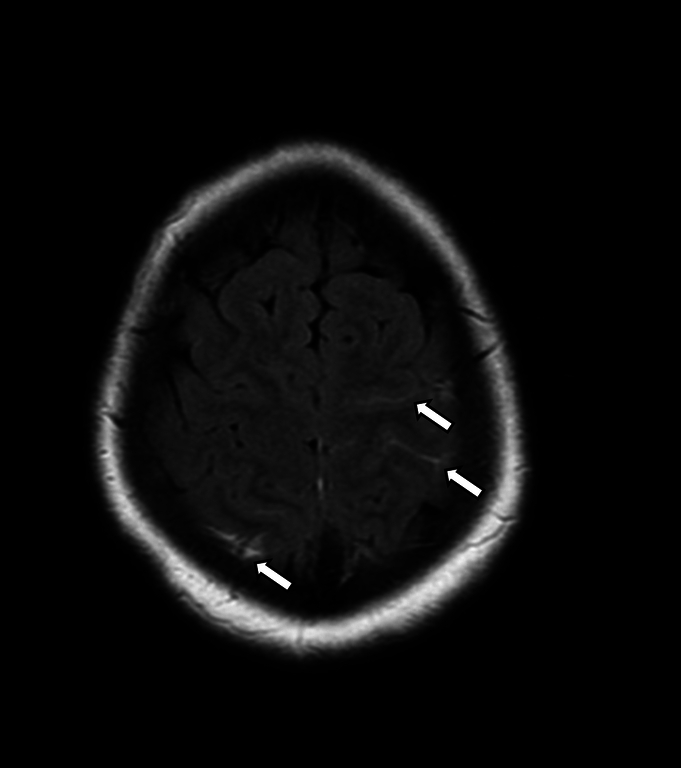

Case report: This case report describes a young woman with CVST who did not respond to low-molecular-weight heparin (LMWH). The patient was initially treated with LMWH; however, her symptoms and clot burden in the sagittal sinus worsened, and coagulation studies showed no evidence of therapeutic anticoagulation despite good compliance. Unfractionated heparin was then initiated, and the patient's symptoms improved dramatically within 24 hours, along with the recanalization of the cerebral venous sinuses. Genetic testing revealed a heterozygous mutation in the prothrombin gene (G20210A). This mutation is a known risk factor for CVST. However, it is unclear why the patient did not respond to LMWH but responded appropriately to unfractionated heparin.

Abstract Image